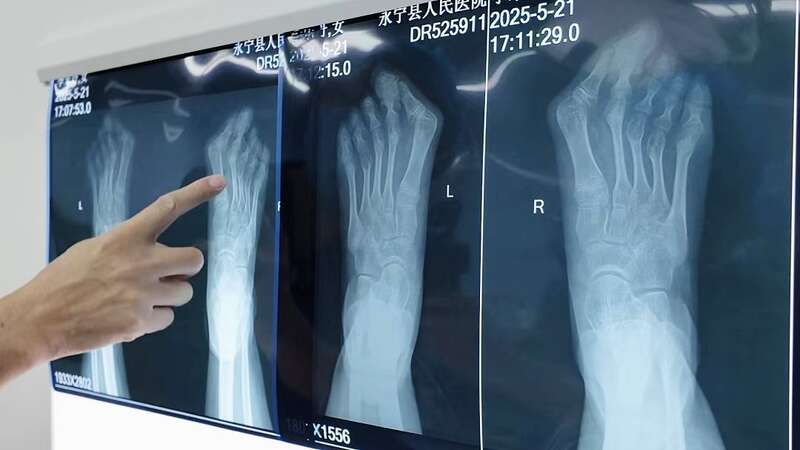

中国青年报客户端讯(吴梦婷 中青报·中青网记者 焦敏龙)5月29日,宁夏回族自治区银川市永宁县人民医院望远院区手术室内,福建省厦门市第三医院足踝外科、手外科主任肖松带领医疗团队,为永宁县1名患有严重“拇外翻”的学生祺祺(化名)开展义诊手术。术后,祺祺不再受足部畸形困扰、重获健康行走的希望。

肖松介绍说:“我们远程指导永宁县人民医院做了术前准备、制订了详细的手术计划,5月28日晚9点多赶到永宁县人民医院望远院区,见到了患者,又讨论了一遍(手术)方案。”